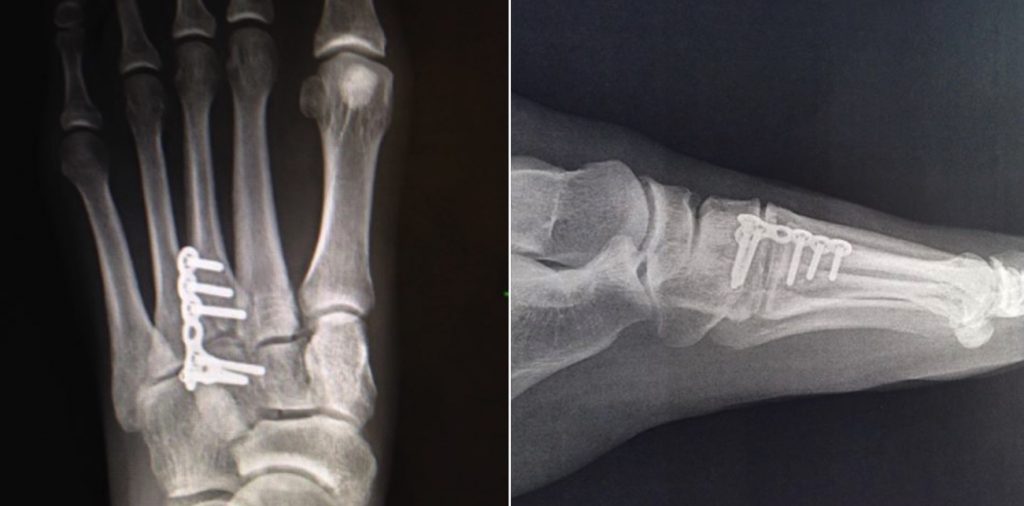

“I had a bone graft as well as plates and screws along the bone to fuse it to the joint, which stayed in for four months. This made me immobile because the plate was across the joint so I couldn’t walk on it without pain and I always felt anxious about risk of snapping it inside my foot,” she said.

In November 2016, the plate and screws were removed during her final surgery. Duncan welcomed her new and improved foot.